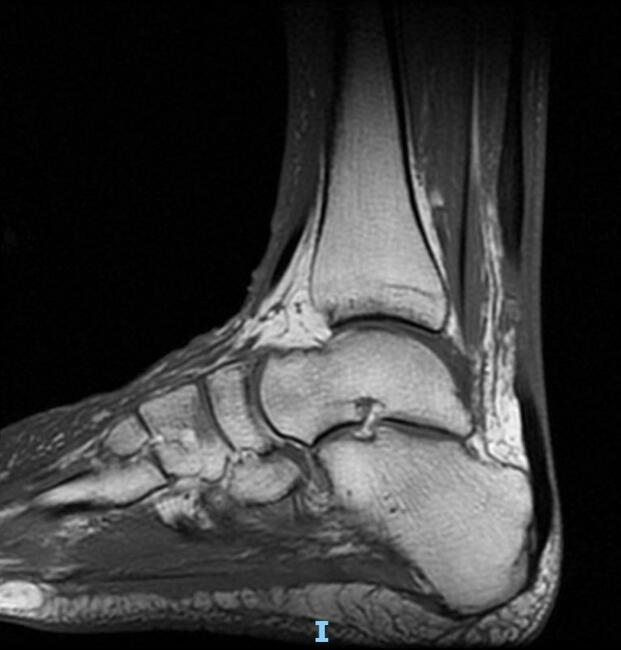

A physical exam revealed edema bilateral to the lower extremities with ecchymosis on the left side but not on the right lower extremity. The patient was neurovascularly intact, and the exam revealed a positive Thompson test on the bilateral lower extremities with no active ankle plantarflexion on the left and right sides. There was a palpable delve in the Achilles on both sides. An MRI that day on both lower legs revealed bilateral Achilles tendon ruptures with a left gap of 3.5cm and a right gap of 2.5 cm.